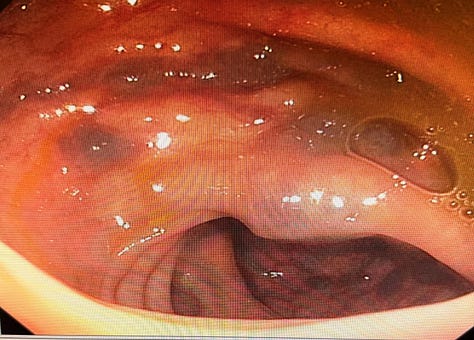

Case 3: A Rare Finding - Blue Rubber Bleb Nevus Syndrome

Case Summary: A series of images showcased the characteristic lesions of Blue Rubber Bleb Nevus Syndrome, a rare vascular disorder.

Key Teaching Points:

•Recognizing the Syndrome: This case served as a great reminder of the endoscopic appearance of this rare syndrome, which is characterized by multiple blue or purple vascular nevi throughout the GI tract and skin.

•Clinical Significance: These lesions can be a source of chronic gastrointestinal bleeding and anemia.